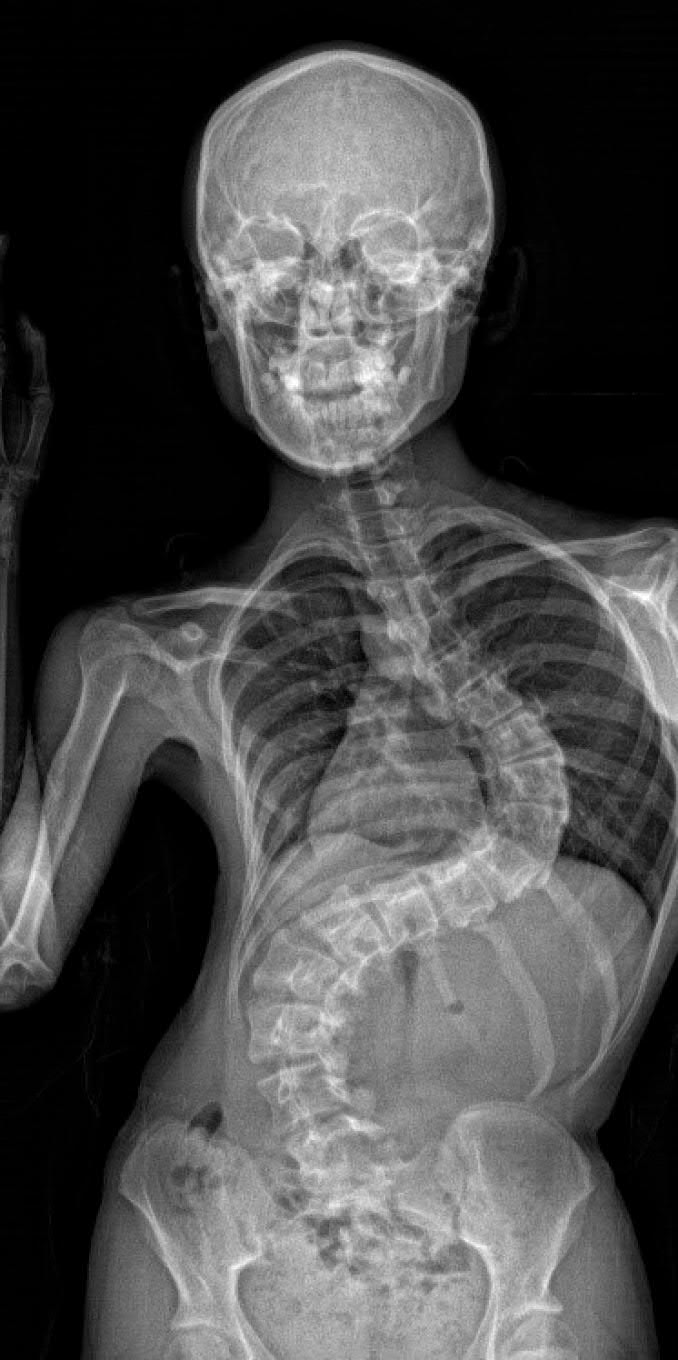

患者在接受脊柱側(cè)彎治療手術(shù)前的X光片。